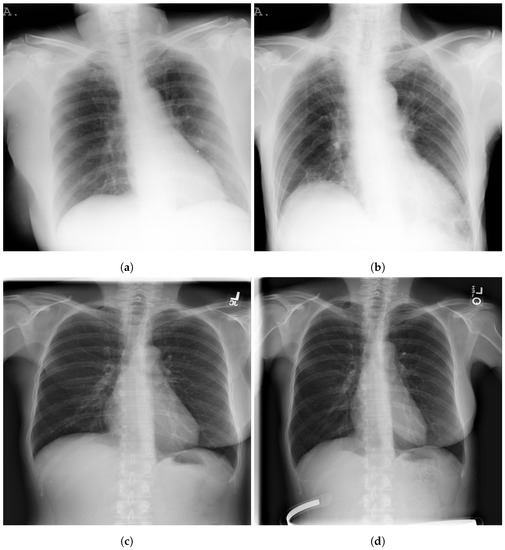

Figure 2 shows examples of SIIM-COVID-19 and RSNA CXR images.

Figure 2. Examples of CXR images; SIIM-COVID-19: (a,b) and RSNA: (c,d).